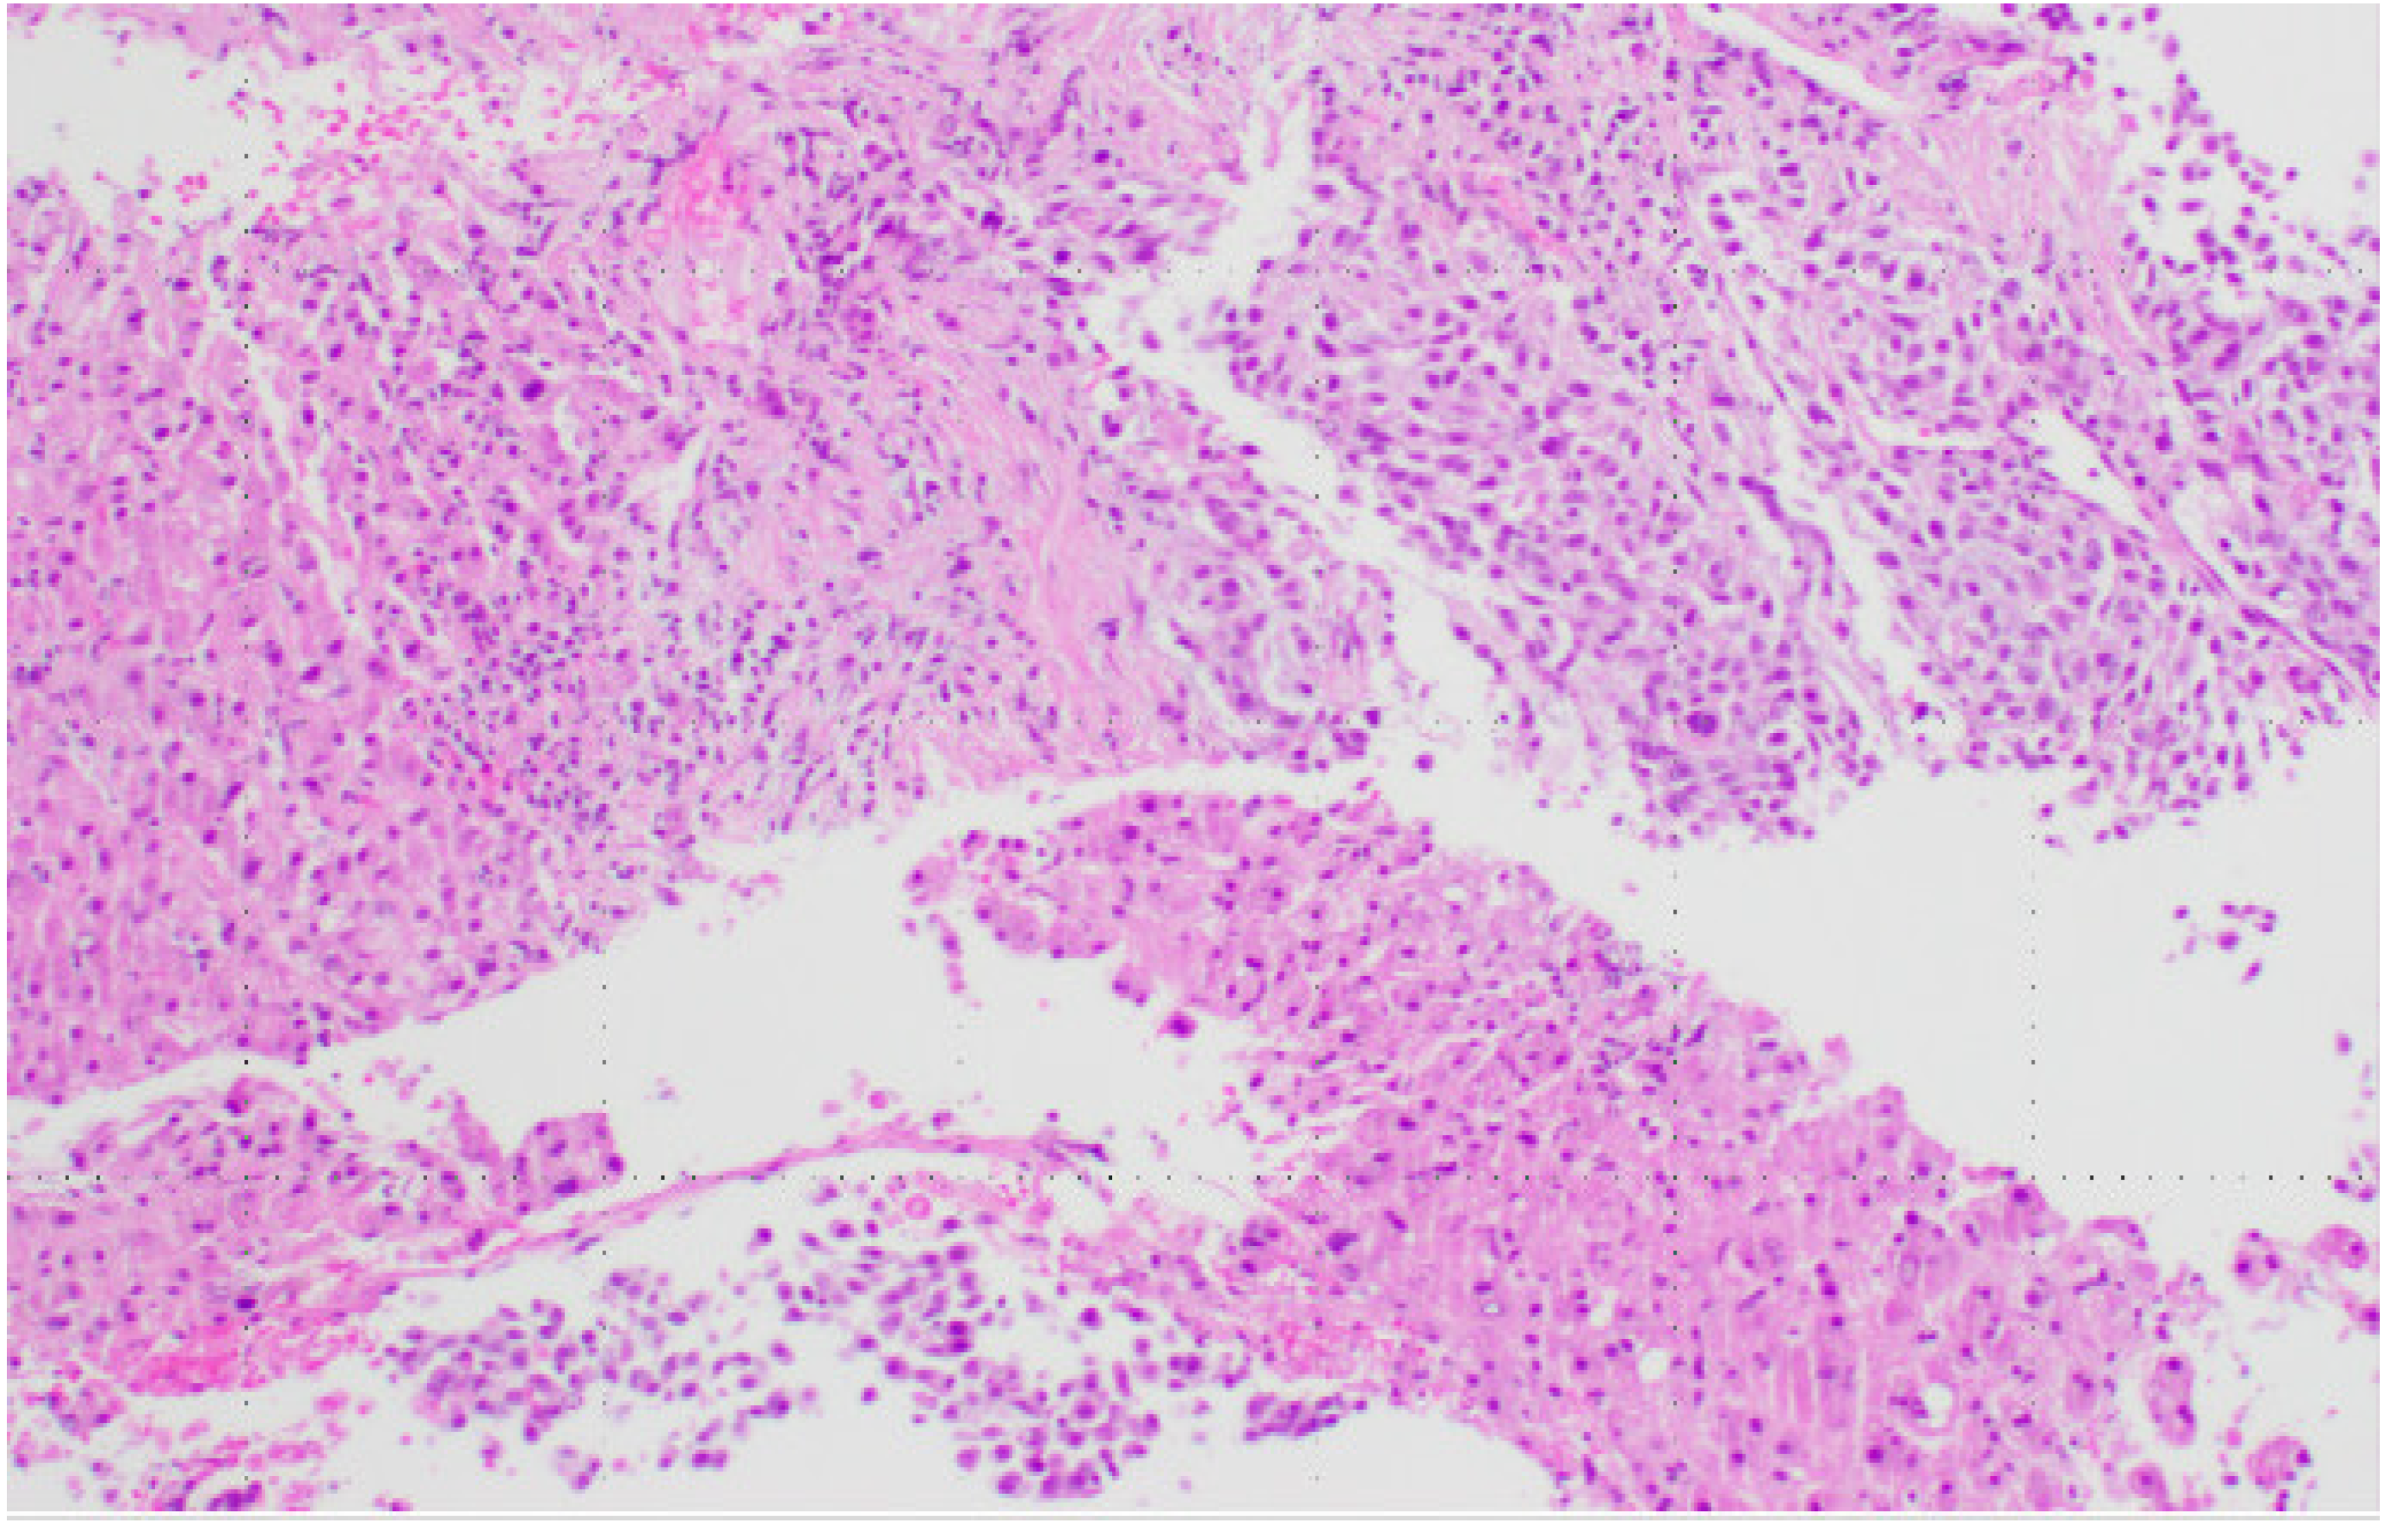

The clinical team decided to perform an ultrasound-guided fine-needle aspiration and biopsy of one of the liver lesions. Touch preparation (Figure 4: DiffQuick, 200X power field) and the biopsy (Figure 5: H&E, 100X power field) showed sheets of malignant epithelioid cells with a high nuclear-to-cytoplasmic ratio, vacuolated eosinophilic cytoplasm, areas of necrosis (Figure 6: H&E, 400X power field), and up to five mitoses per one high-power field (Figure 7: H&E, 400X power field).

Figure 5.

H&E, 100X. Ultrasound-guided fine-needle aspiration and biopsy of one of the liver lesions with sheets of malignant epithelioid cells.